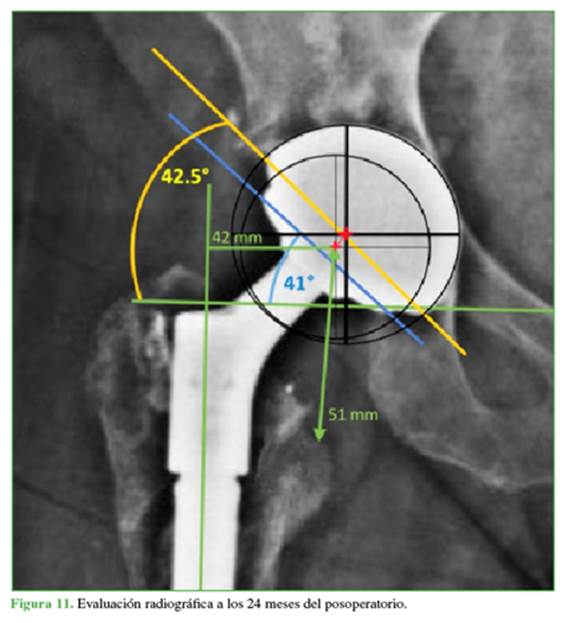

En el análisis radiológico posquirúrgico de la placa, se evidenció un incremento del offset horizontal, que pasó de 39 mm a 42 mm por el uso del offset extendido. Esto se determinó por el método por Bellova y cols.,16 en el cual se traza una línea que une los centros de rotación independientes de la copa no cementada y la copa DM. Al tener una orientación independiente, la copa DM presenta una inclinación de 41,3°, diferente de la copa no cementada (42,7°), lo que optimiza la inclinación y la anteversión. Se mejoró la discrepancia de miembros hasta lograr una diferencia de solo 1 mm (Figura 10). En la evaluación radiográfica a los 24 meses del procedimiento, se evidenció la consolidación completa del fémur proximal y no se encontraron cambios en los valores de inclinación, anteversión y offset, ni signos de aflojamiento en la interfaz entre la copa no cementada y la copa DM. Del mismo modo, no se observaron signos de aflojamiento en ninguno de los componentes (Figura 11).

El uso de copas DM parece ser una buena alternativa cuando hay inestabilidad protésica. En el caso presentado, se modificó el módulo proximal del implante femoral; el offset conseguido pasó de 39 mm a 42 mm y el cambio del módulo permitió compensar longitud. Además, el ángulo de inclinación logrado con la copa DM fue de 41,3° comparado con los 42,7° de la copa no cementada. Esta variación de 1,4° no debería considerarse influyente para disminuir el índice de luxación. Por tanto, se podría inferir que es por sus características propias, ya referidas por otros autores, que la copa DM es una alternativa válida para el manejo de la inestabilidad protésica.